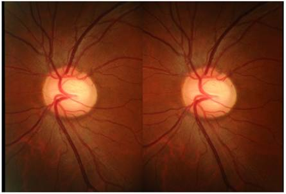

视盘的评估

与此同时,以下视神经盘的评估可帮助患者发现其他暂无症状、但有健康风险的疾病,如早期青光眼或脑肿瘤。这可能会帮助挽救患者的健康和生命。

- 视盘的边界;

- 视盘的颜色;

- 杯盘比:视杯纵轴长度和视盘纵轴长度的比值(十分位比值);

- 盘沿出血;

- 局限性视神经纤维束缺失。

▲ 视杯扩大:图中大视杯的杯盘比达到了7/10或0.7

▲ 局限性视神经纤维束缺失